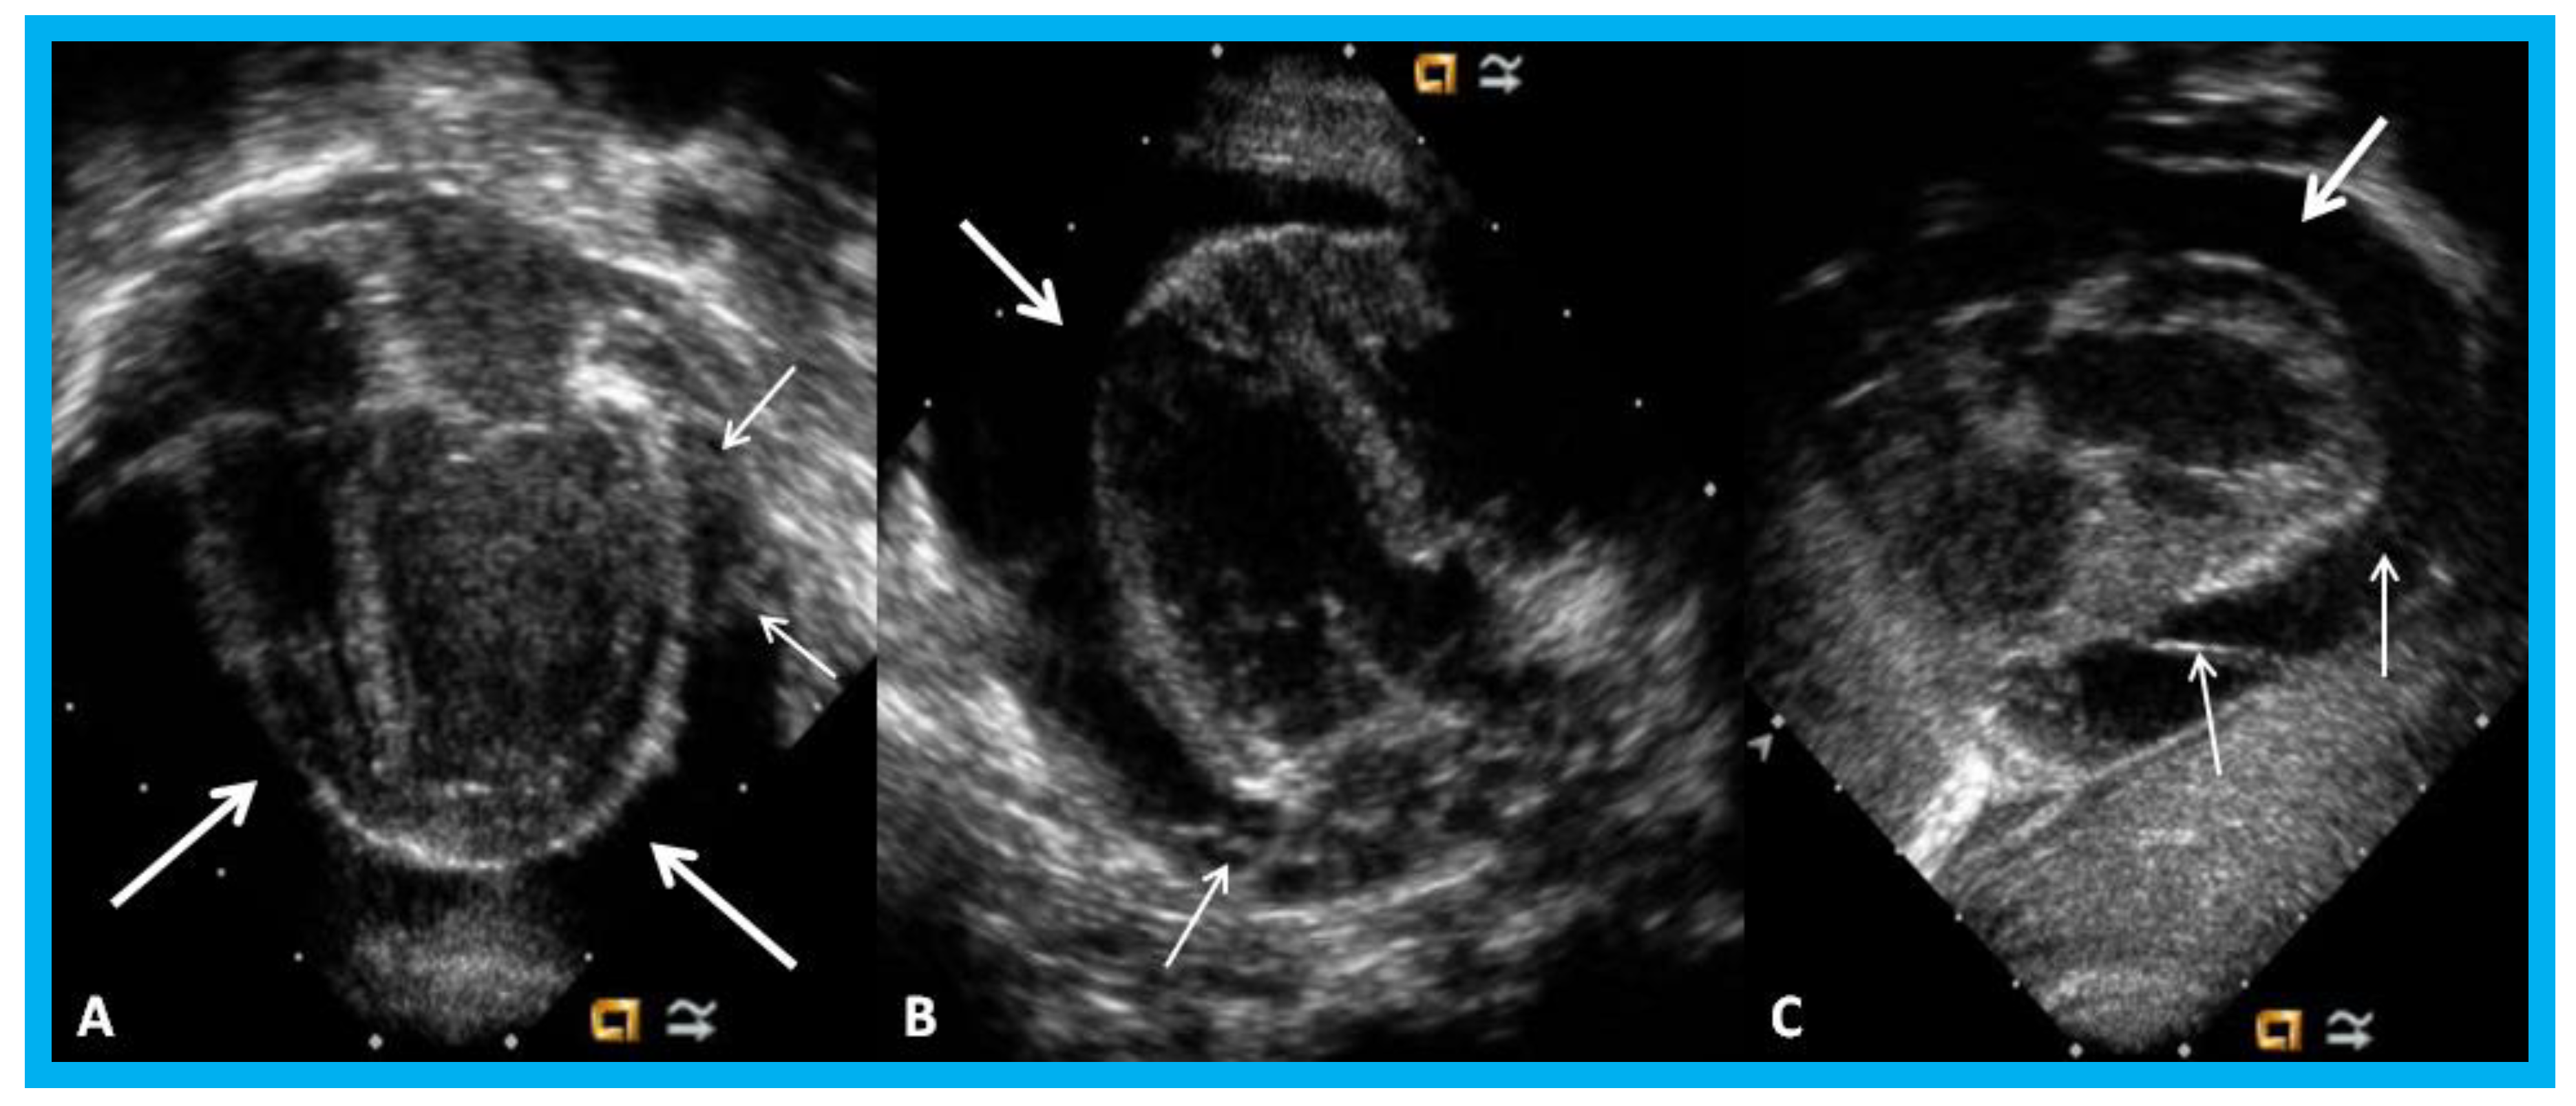

Figure 30. Apical four-chamber (A,B) and parasternal short axis (C) views of the heart in an infant with cardiomegaly showing a significant pericardial effusion (thick arrows): Fibrin strands in the effusion are shown (thin arrows).